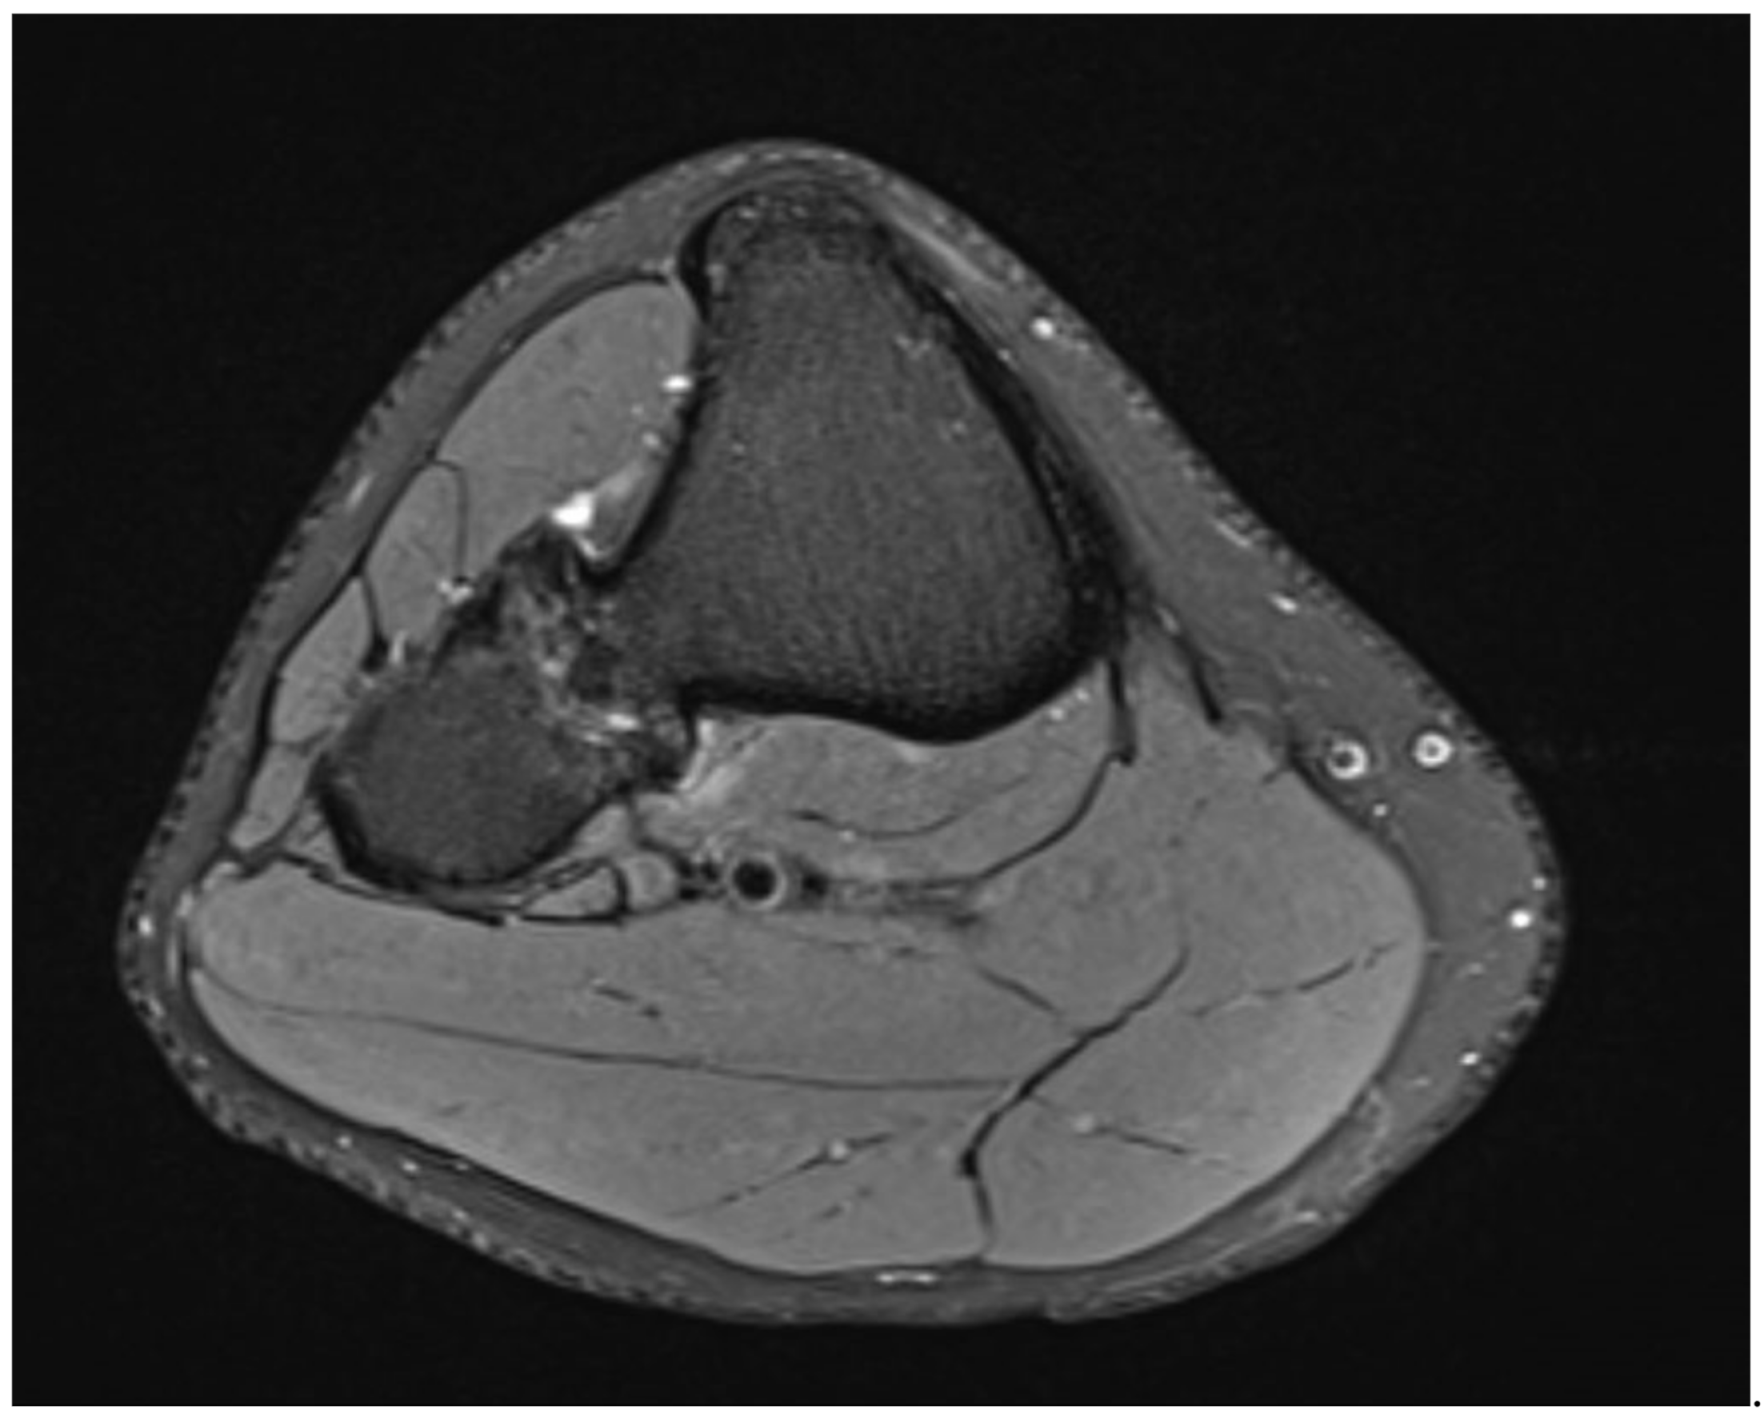

Plain radiographs, performed in anterior-posterior and lateral views of both knees showed a bony excrescence originating from the lateral tibial condyle as well as from the head of the fibula (Figure 1). The joint space was hardly visible. There were no signs of fracture or osteolysis.

Figure 1. Plain radiograph in a.-p. view showing the bilateral synostosis.